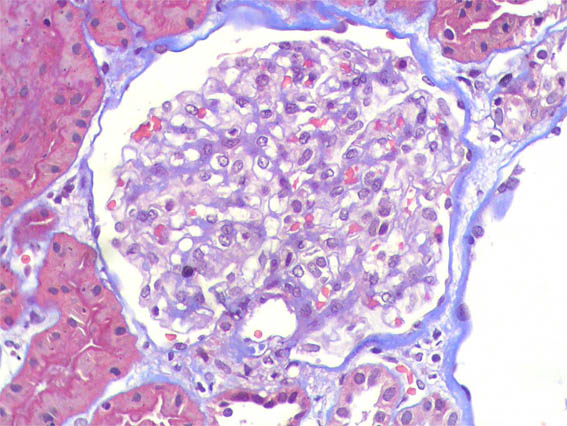

Figure 8. PAS, X200.

Figure 10. Masson's trichrome staining, X400.